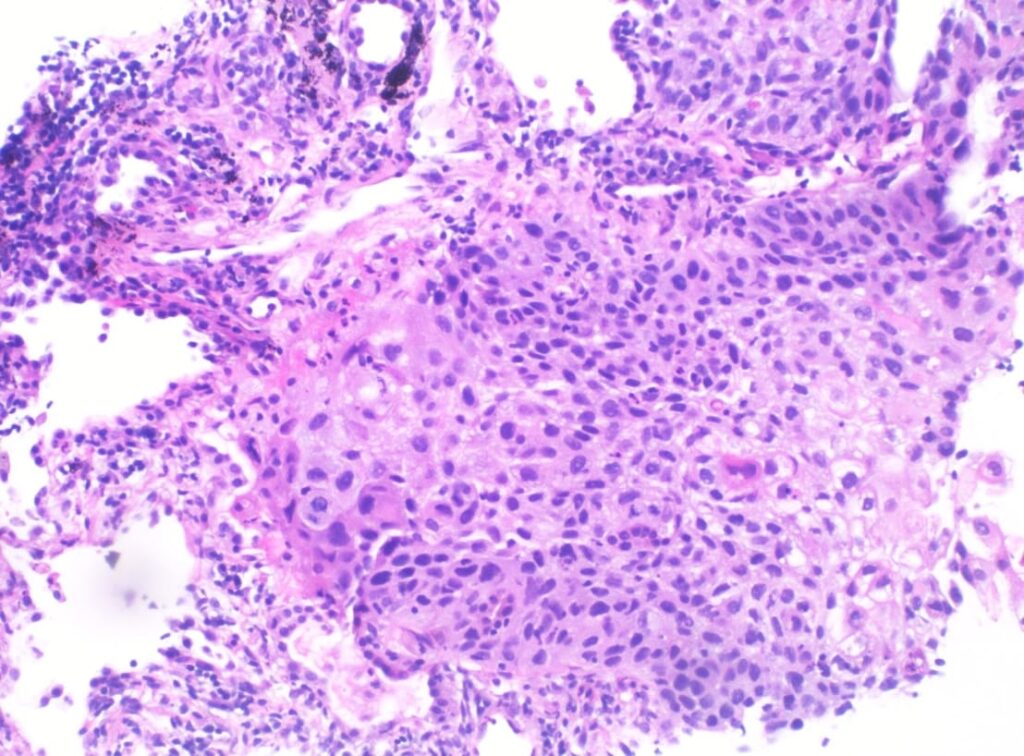

Hiperplasia adenomatosa atípica del pulmón

Adenomatous hyperplasia atypical of the lung Resumen Paciente hombre de 74 años con un cuadro de dos meses de tos...